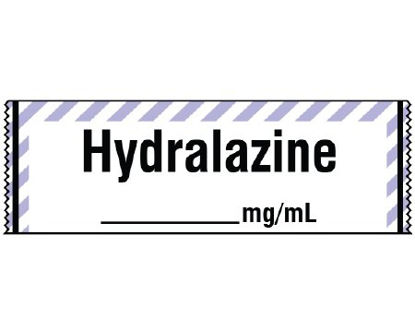

SKU #

#1132690

MPN #

CKG032519

Brand

Shamrock Scientific

Stock

In Stock

Quantity

100